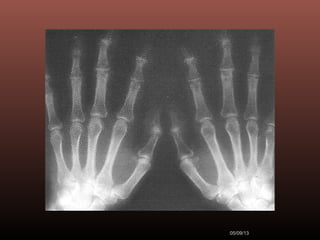

 Ao exame está em bom estado geral, corada,

hidratada. Apresenta pequenos nódulos endurecidos e

com leve dor a palpação em interfalangeanas distais

(Fig 1) crepitação à movimentação do polegar direito

Figura l

Exames Radiográficos

 No início da doença não se observam

anormalidades. Com seu

desenvolvimento, observam-se:

1-Diminuição do espaço intra-articular

2-Esclerose subcondral (eburnação)

3-Osteófitos;

4-Erosão e anquilose óssea

(pseudocistos ósseos).